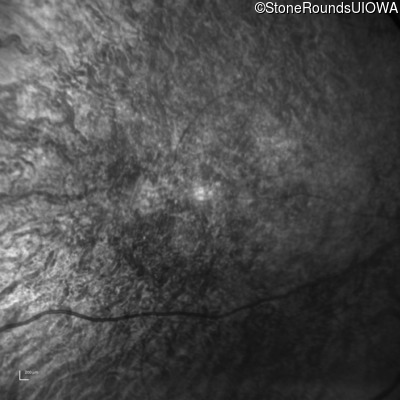

This 41 year old man first came to medical attention at age 18 months when exotropia and amblyopia of his right eye were discovered. At age 11 vitreous strands and retinal vascular sheathing were seen. He has had poor night vision and constricted visual fields since his late teens. Later, at age 44 a traction retinal detachment was noted in his left eye and was treated with a scleral buckle.

Age at visit: 41 years